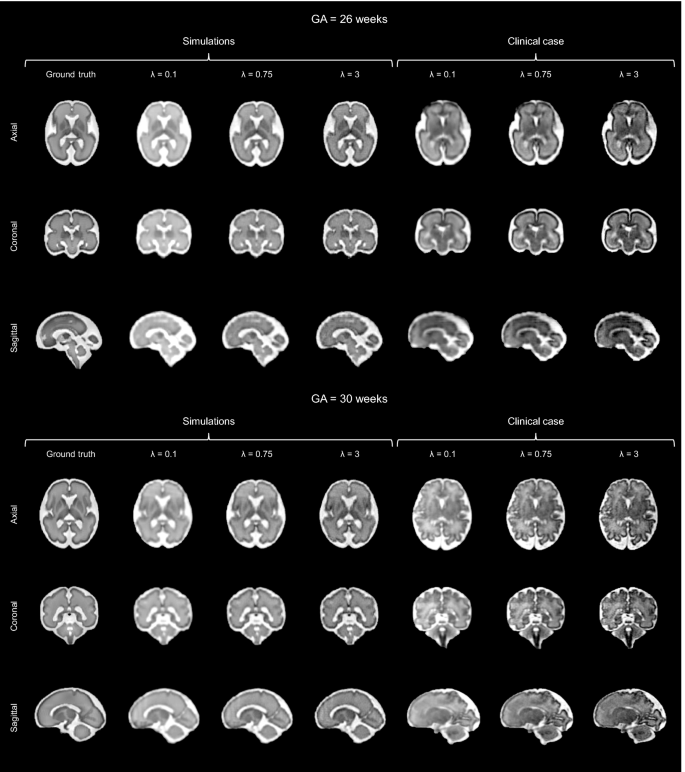

Thanks to its controlled environment, FaBiAN makes it possible to adjust the parameter \(\lambda\) for optimal SR reconstruction with respect to a simulated 3D isotropic HR ground truth of the fetal brain. Figure 3 explores the quality of SR fetal brain MRI from LR HASTE images corrupted by motion depending on the weight of TV regularization in two subjects of 26 and 30 weeks of GA respectively. Based on the simulations, a high level of regularization (\(\lambda = 0.1\)) provides a blurry SR reconstruction with poor contrast between the various structures of the fetal brain, especially in the deep gray nuclei and the cortical plate. In addition, the cerebrospinal fluid appears brighter than in the reference image. A low level of regularization (\(\lambda = 3\)) leads to a better tissue contrast but increases the overall amount of noise in the resulting SR reconstruction. A fine-tuned regularization (\(\lambda = 0.75\)) provides a sharp reconstruction of the fetal brain with a high SNR and a tissue contrast close to the one displayed in the reference image. In the SR images reconstructed from clinical LR HASTE series altered by a little-to-moderate level of motion, as in the simulations, the structure of the corpus callosum and the delineation of the cortex are especially well defined for appropriate TV regularization (\(\lambda = 0.75\)), leading to high-SNR HR images of the fetal brain. Although the NRMSE between SR reconstructions from simulated HASTE images and the corresponding ground truth are close to each other for a given GA across the various weights studied, Fig. 4 shows that the error is systematically minimal for \(\lambda = 0.75\), which further supports this parameter setting for optimal SR reconstruction of the fetal brain from this type of MR images.

Appreciation of the quality of SR reconstruction depending on the weight \(\lambda\) that controls the strength of the TV regularization. The potential of our framework FaBiAN for optimizing the reconstruction quality through parameter fine-tuning in the presence of motion is illustrated at two GA: 26 and 30 weeks. Two representative clinical cases are provided for comparison. The results for three values of \(\lambda\) are presented. For \(\lambda = 0.1\), the SR reconstruction looks blurry with poor tissue contrast. Using \(\lambda = 3\) improves the contrast but the images look noisy. For \(\lambda = 0.75\), the SR reconstruction is sharp with a contrast between different brain tissues similar to that observed in the 3D isotropic ground truth. Clinical cases from which the simulated HASTE images are derived highlight the accuracy of a SR reconstruction for this intermediate value of \(\lambda\), especially with regards to the definition of the corpus callosum and the delineation of the cortex.